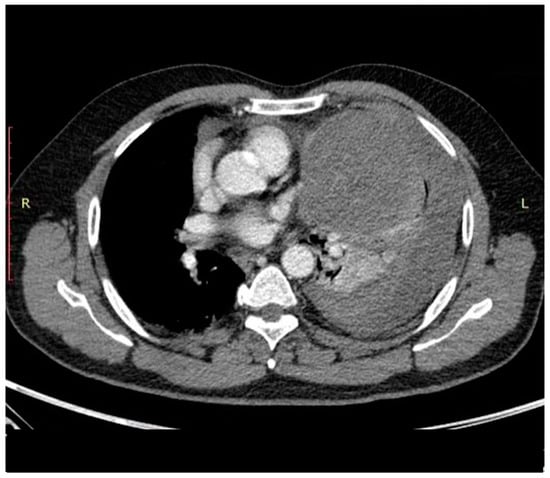

- Aroshidze, B.; Boyapati, L.; Pokhrel, A.; Gotlieb, V.; Khan, A.; Erdinc, B.; Cheema, M.A. Yolk Sac Tumor in the Anterior Mediastinum Presenting as Acute Pericarditis. Am. J. Case Rep. 2022, 23, e932616. [Google Scholar] [CrossRef]